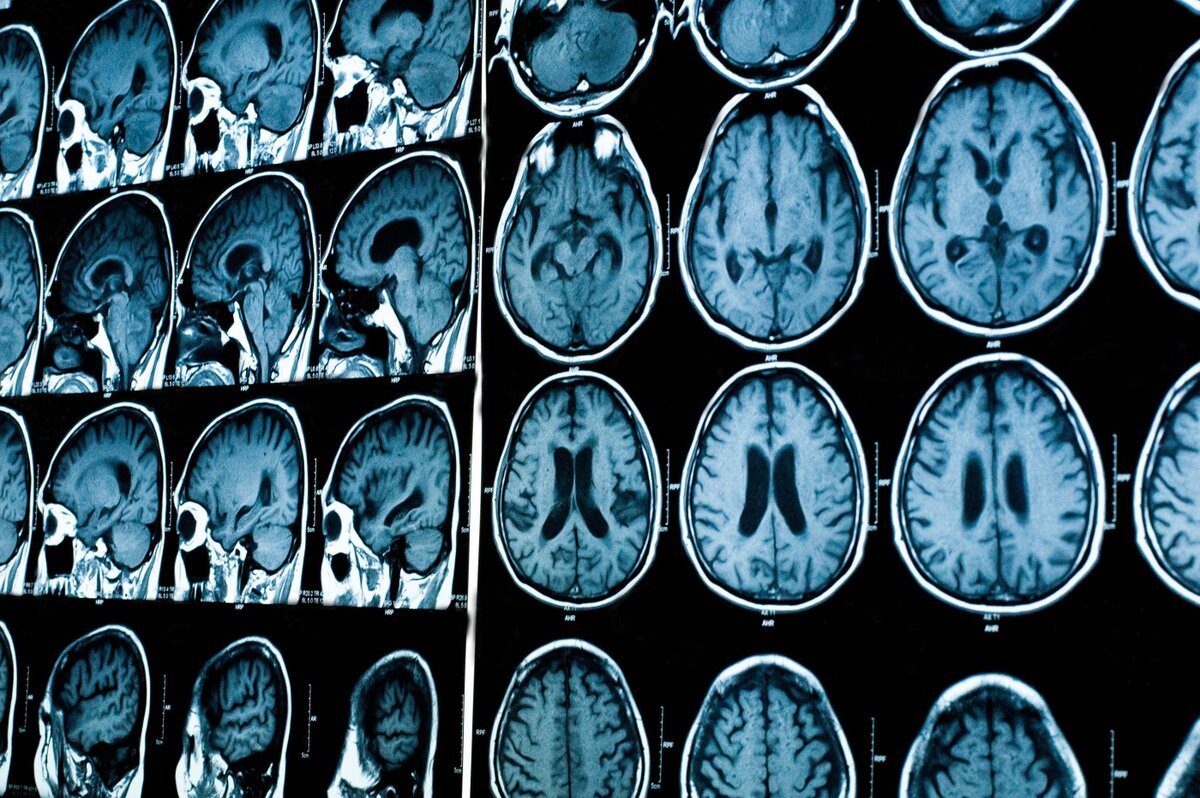

Принцип работы магнитно-резонансной томографии: Основы и преимущества

Эти слабые сигналы регистрируются МРТ-сканером и обрабатываются компьютерной системой. Компьютер использует полученные данные для создания изображений, которые отображают структуру и состояние тканей и органов пациента. Как результат, врачи получают детальные срезы исследуемой области тела, позволяющие им обнаружить патологии и провести точную диагностику.

Преимущества МРТ заключаются в том, что она не использует ионизирующее излучение, что позволяет снизить риски для пациентов. Метод также обладает высокой разрешающей способностью, позволяющей врачам увидеть мелкие изменения в тканях и органах, которые могут оставаться незамеченными при других методах исследования. Кроме того, МРТ позволяет получить изображения в различных плоскостях и создать трехмерные реконструкции, что помогает врачам более полно и точно оценить состояние организма пациента.